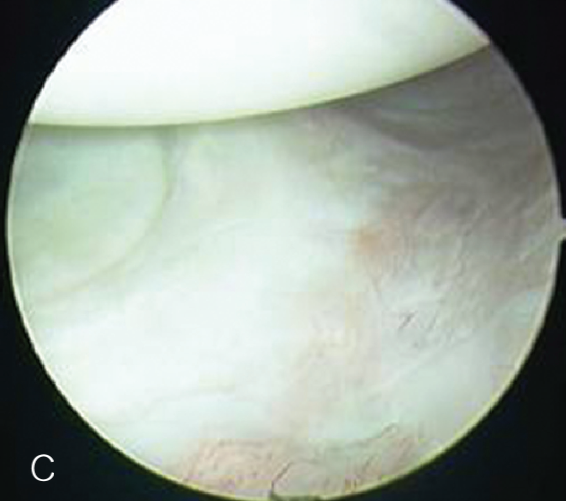

修复处准备